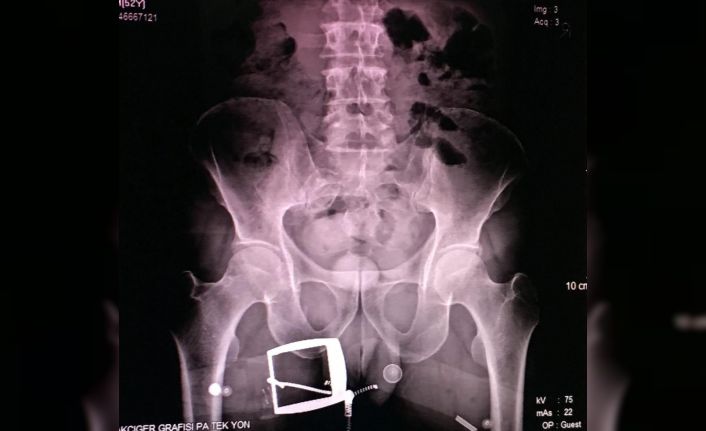

Erzurum Emniyet Müdürlüğü Kaçakçılık ve Organize Suçlarla Mücadele (KOM) Şubesi ekipleri, uygulama sırasında durdurdukları bir yolcu otobüsünde arama yaptı. İranlı B.H.’ye ait olduğu anlaşılan valizde, 21 parçadan oluşan ve ‘met’ olarak bilinen 607 gram ‘metamfetamin’ maddesi ele geçirildi. Gözaltına alınan B.H.’nin hareketlerinden şüphelenen narkotik polisi, kendisini sağlık kontrolü için hastaneye götürdüğünde röntgen çekilmesini de istedi. Röntgen filmi sonuçlarında İranlı kadının uyuşturucuyu kapsüller halinde makatına soktuğu anlaşıldı.

Tıbbi müdahaleyle 4 kapsül halinde 96 gram ‘met’ ve bir kapsülde 28 gram reçine esrar çıkarılırken, uyuşturucunun piyasa değerinin 50 bin lira olduğu belirtildi. İranlı B.H. tutuklanarak cezaevine konuldu.